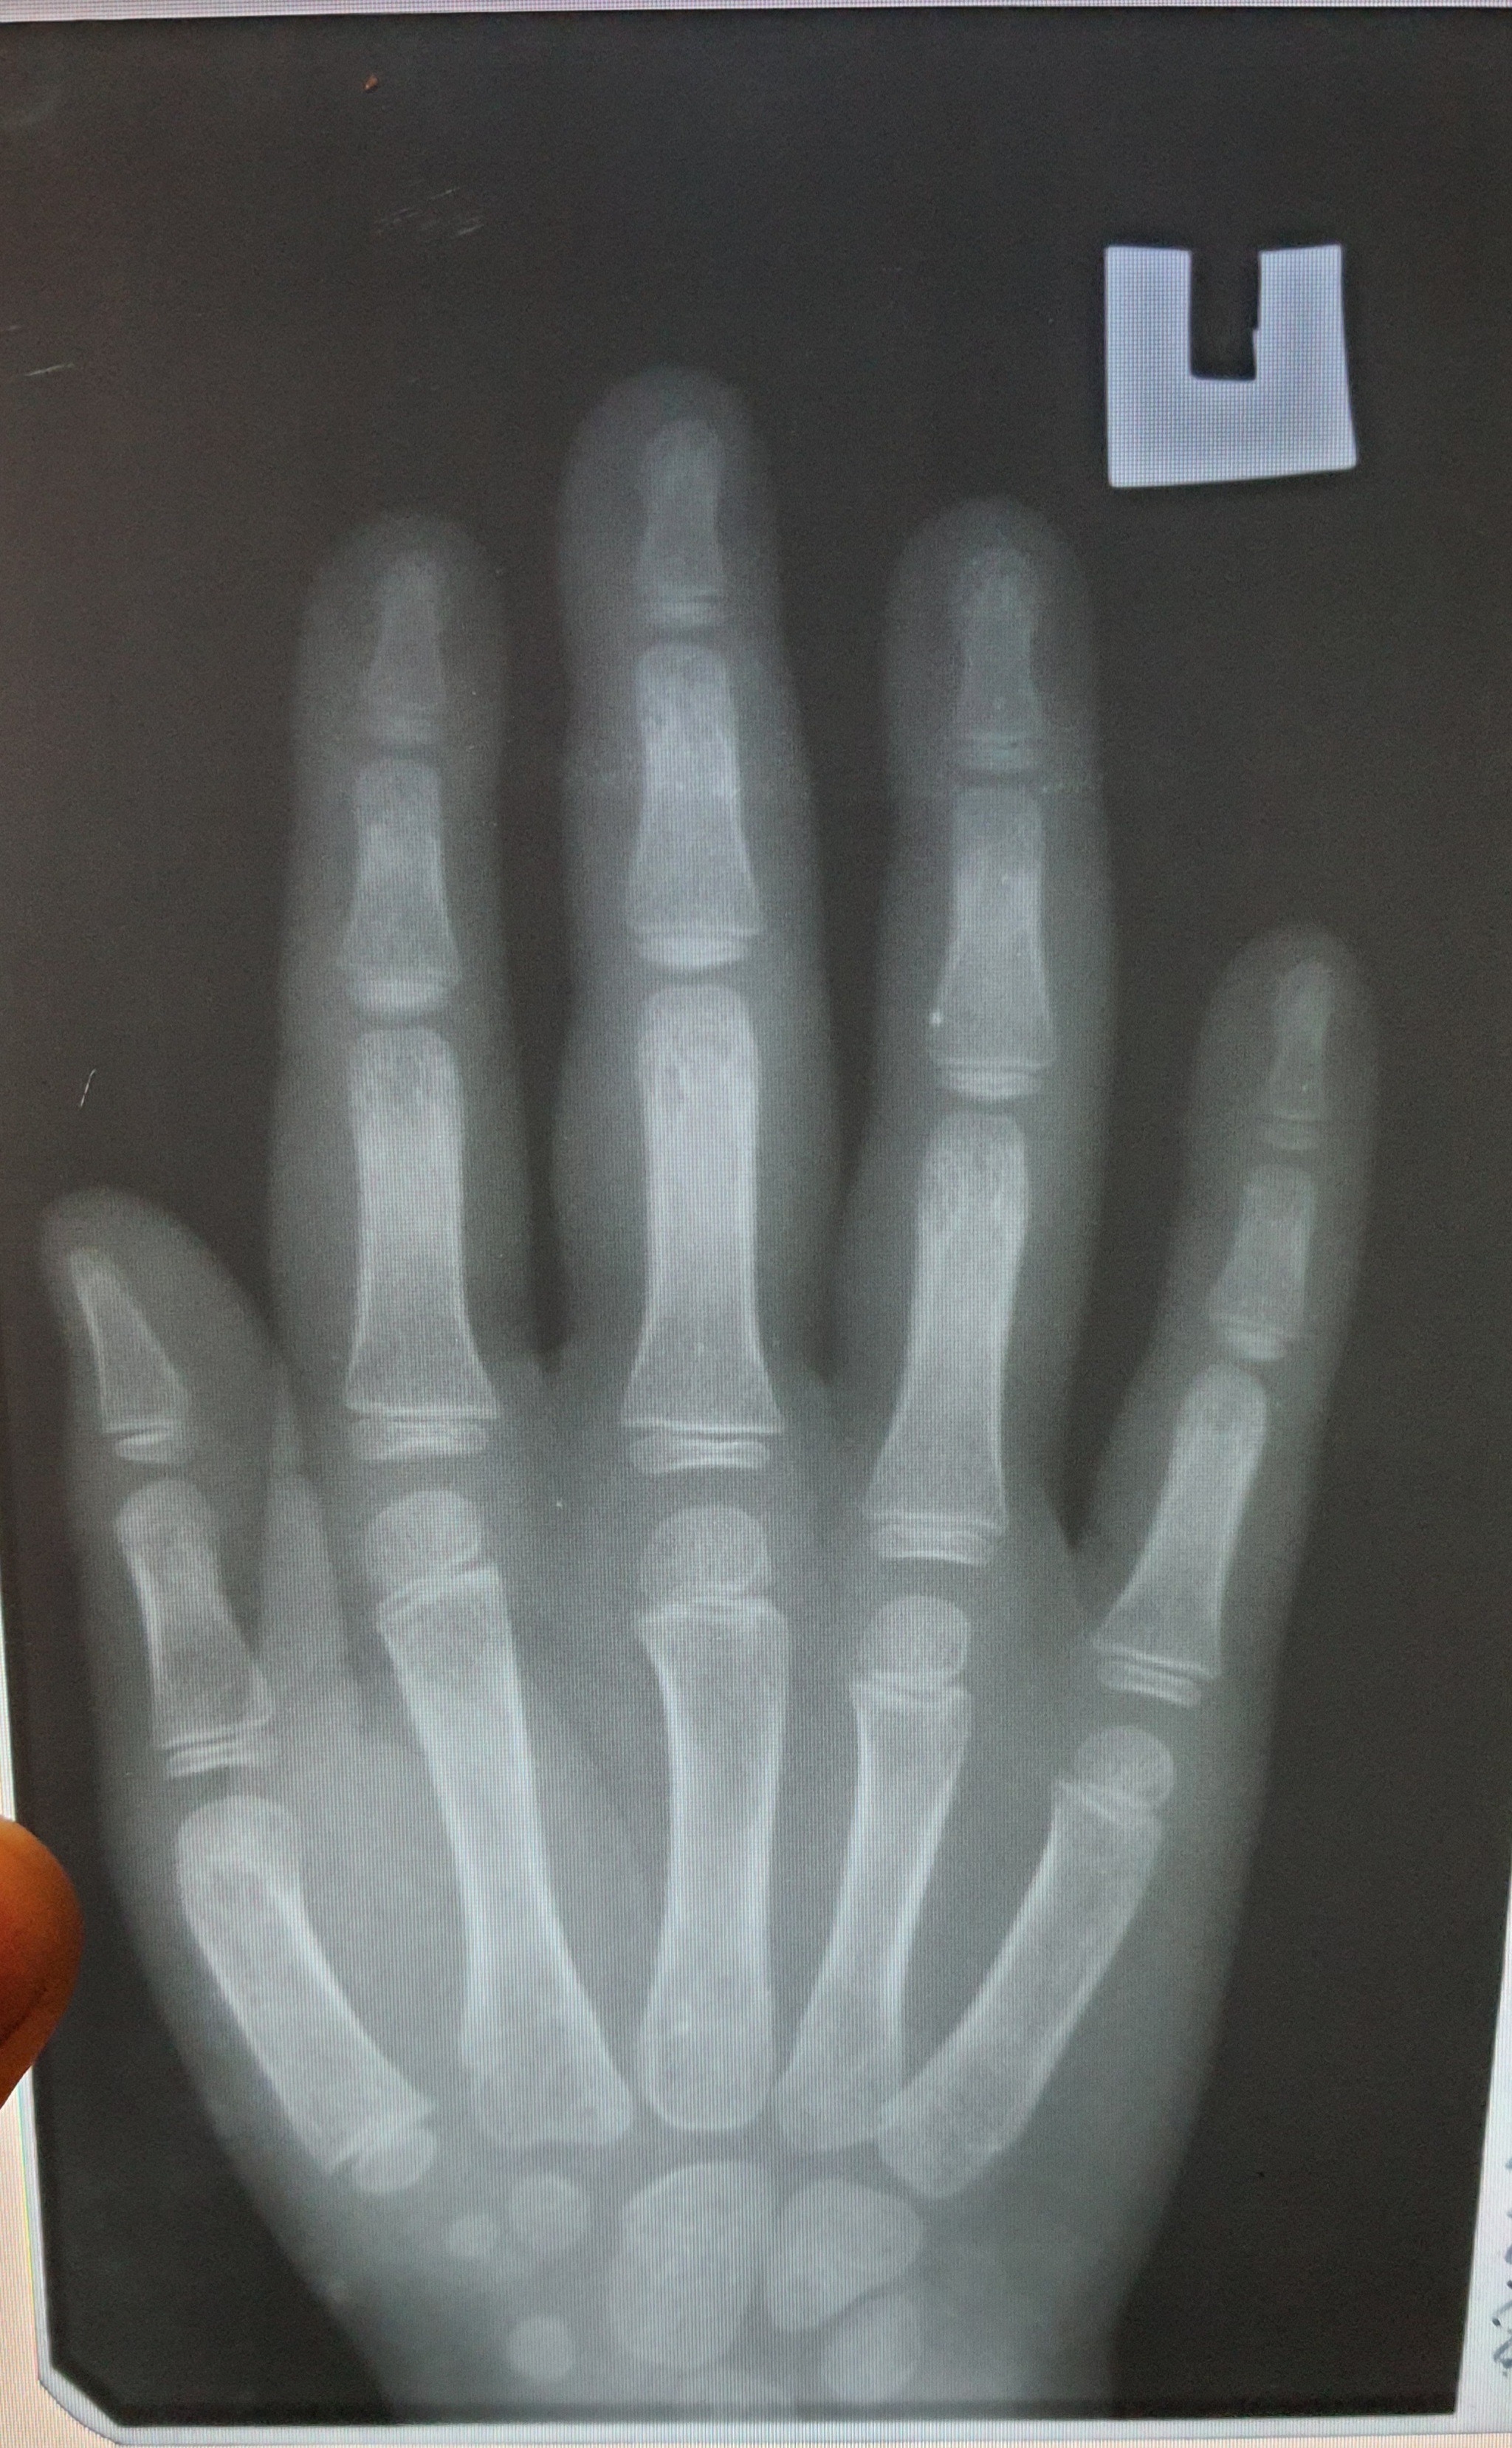

Вы видите перелом?

Я нет. А он говорят есть. А где есть пальцем не ткнули, не показали. Помогите увидеть.